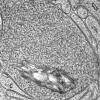

PERIPHERAL NEUROPATHY

5 AXONAL REGENERATION (8)